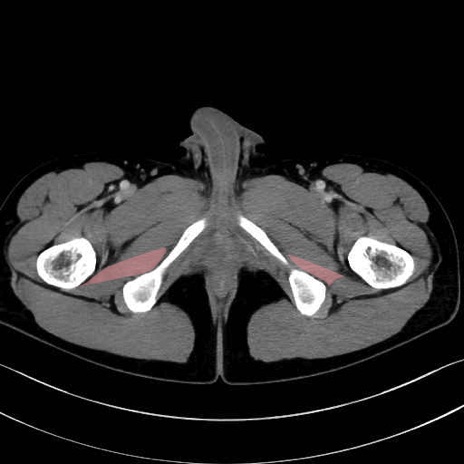

外閉鎖筋 (Obturator externus)